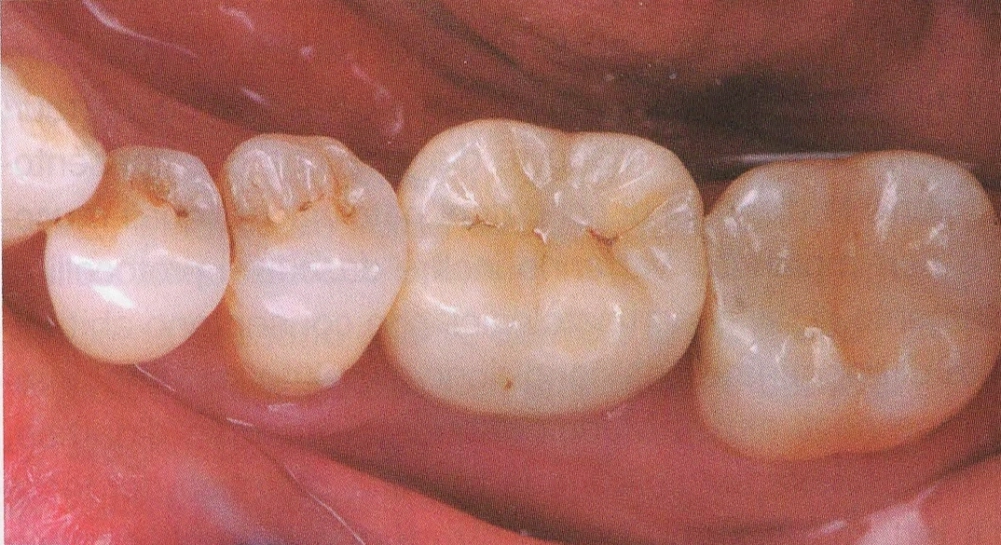

CERAMICHE SU IMPIANTI

In questo studio vengono eseguite ceramiche di ultima generazione quali la zirconia ceramizzata, le ceramiche estetiche in disilicato senza trascurare le tradizionali metalceramiche. Il disilicato è un materiale altamente estestico che conferisce alla corona protesica un aspetto naturale e con questo materiale si possono creare manufatti con uno spessore molto ridotto.